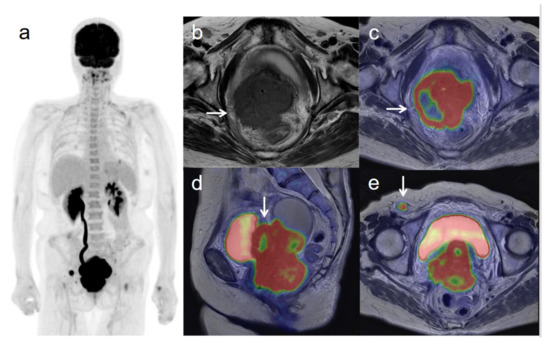

Figure 1. A 54-year-old woman with stage IIIC1 cervical cancer with parametrial invasion. (a) 18F-FDG PET image shows FDG uptake by tumor in the cervical cervix (arrow) and pelvic lymph nodes. (b) Axial T2-weighted pelvic MR image shows parametrial invasion with disruption of the right cervical stroma by the tumor but no extension into the pelvic side wall (arrow). (c) Axial T2-weighted PET/MR image shows FDG uptake by the tumor, which invades the right parametrium with disruption of the cervical stroma, but no extension into the pelvic side wall (arrow). These appearances are consistent with the clinical findings. (d) Sagittal T2-weighted PET/MR image shows FDG uptake by the cervical tumor. (e) Coronal T2-weighted PET/MR image shows FDG uptake by the cervical tumor and pelvic lymph nodes (arrows).

The overall accuracy of revised FIGO staging for 18F-FDG PET/MRI and MRI/CT was 69.4% (50/72) and 50.0% (36/72), respectively (significant difference, p < 0.001). When we excluded patients diagnosed by conization to focus on the revision points, the accuracy of the revised 2018 FIGO staging was also significantly better for 18F-FDG PET/MRI (82.1%, 46/56) than for MRI/CT (60.7%, 34/56) (p < 0.01). 18F-FDG PET/MRI understaged the actual stage in 17 patients (23.6%), whereas MRI/CT resulted in understaging in 31 patients (43.1%). 18F-FDG PET/MRI incorrectly classified eight IA and four IB1 tumors as no tumors; two IIB tumors as IB1; one IIIB tumor as IIB; and two IIIC1 tumors as IB2 and IIA2; whereas MRI/CT incorrectly classified eight IA and seven IB1 tumors as not tumors; two IIB tumors as IB1; one IIIB tumor as IIB; nine IIIC1 tumors as IB1, IB2, IIA2, and IIB; two IIIC2 as IIIC1, and two IVB as IIA2 and IIIC1. 18F-FDG PET/MRI or MRI/CT overstaged the actual stage in five patients (6.9%). 18F-FDG PET/MRI or MRI/CT incorrectly classified one IB1 tumor as IIA1, two IB2 tumors as IIB and IIIC1, one IIA2 tumor as IIB, and one IIIC1 tumor as IIIC2. Sensitivity, specificity, and accuracy for detecting growth into the vagina were 100%, 94.6%, and 97.2%, respectively, for both 18F-FDG PET/MRI and MRI (p = 1). Sensitivity, specificity, and accuracy for growth into the parametrium were 88.6%, 97.3% and 93.1% for 18F-FDG PET/MRI; and 88.6%, 94.6%, and 91.7% for MRI, respectively (p = 1). Sensitivity, specificity, and accuracy for growth into the pelvic wall were 83.3%, 100%, and 97.2%, respectively, for both 18F-FDG PET/MRI and MRI (p = 1). Figure 1 and Figure 2 show representative images for the detection of invasion of the parametrium and pelvic side wall. Sensitivity, specificity, and accuracy for pelvic lymph node metastasis were 92.3%, 97.8%, and 95.8% for 18F-FDG PET/MRI; and 57.7%, 97.8%, and 83.3% for CT, respectively (p = 0.008 < 0.01). Sensitivity, specificity, and accuracy for paraaortic lymph node metastasis were 100%, 98.4%, and 98.6% for 18F-FDG PET/MRI; and 75.0%, 98.4%, and 95.8% for CT, respectively (p = 0.480). Figure 3 and Figure 4 show representative images for the detection of pelvic and paraaortic lymph node metastasis. Sensitivity, specificity, and accuracy for growth into adjacent organs such as the bladder or rectum were 100%, 100%, and 100% for both 18F-FDG PET/MRI and MRI (p = 1). Sensitivity, specificity, and accuracy for distant metastasis were 100%, 100%, and 100% for 18F-FDG PET/MRI; and 71.4%, 100%, and 97.2% for CT, respectively (p = 0.480) (Table 2). Figure 5 shows representative images for the detection of distant metastasis.